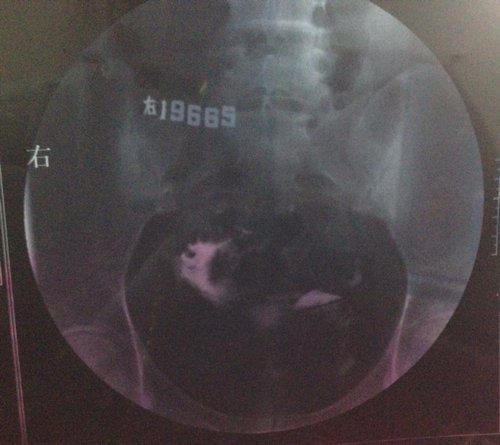

上个月输卵管造影的结果,这个月想试孕又发现卵泡没排出来,现在纠结要不要打促排卵针,片子上看起来严重 上个月输卵管造影的结果,这个月想试孕又发现卵泡没排出来,现在纠结要不要打促排卵针,片子上看起来严重吗?这个月是右卵巢有优势卵泡。医生帮忙看下,我这情况能打促排卵针吗? 点击展开 匿名用户 2014-05-11 00:08 为您推荐: 其他回答 病情分析: 你好,应该予以手术治疗的 指导意见: 可以考虑腹腔镜手术来治疗,术后注意不可过早恢复同房,及时复查。 独水凡_xjeq 2014-05-11 10:34 相关问题 3月做的输卵管造影,两侧通而欠畅,4月做卵泡监测,发现卵泡大了不排,5月刚打了促排卵针,请问我宫外 之前做造影,结果是左侧通,右侧不通,后来做输卵管通液通了,现在右侧卵泡2 1请 请问:(南京鼓楼医院)做(生殖激素测定+基础卵泡检查)跟(子宫输卵管浀造影)跟(甲功三项)大概